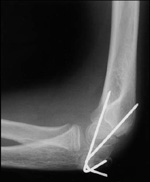

(Left) This child has a severe fracture of the humerus above the elbow. (Right) This x-ray of the fracture shows that the humerus has broken into two parts-a complete displacement.

(Courtesy of Texas Scottish Rite Hospital for Children)

This x-ray shows a supracondylar humerus fracture that has been put into the correct position and held in place with two pins. The pins will be removed after healing has begun.

Reproduced from: Surgical management of pediatric fractures in the upper extremity, Flynn J, Sarwark J, Waters P, Bae D, Lemke L: Instr Course Lect 2003, 54: 635-645.